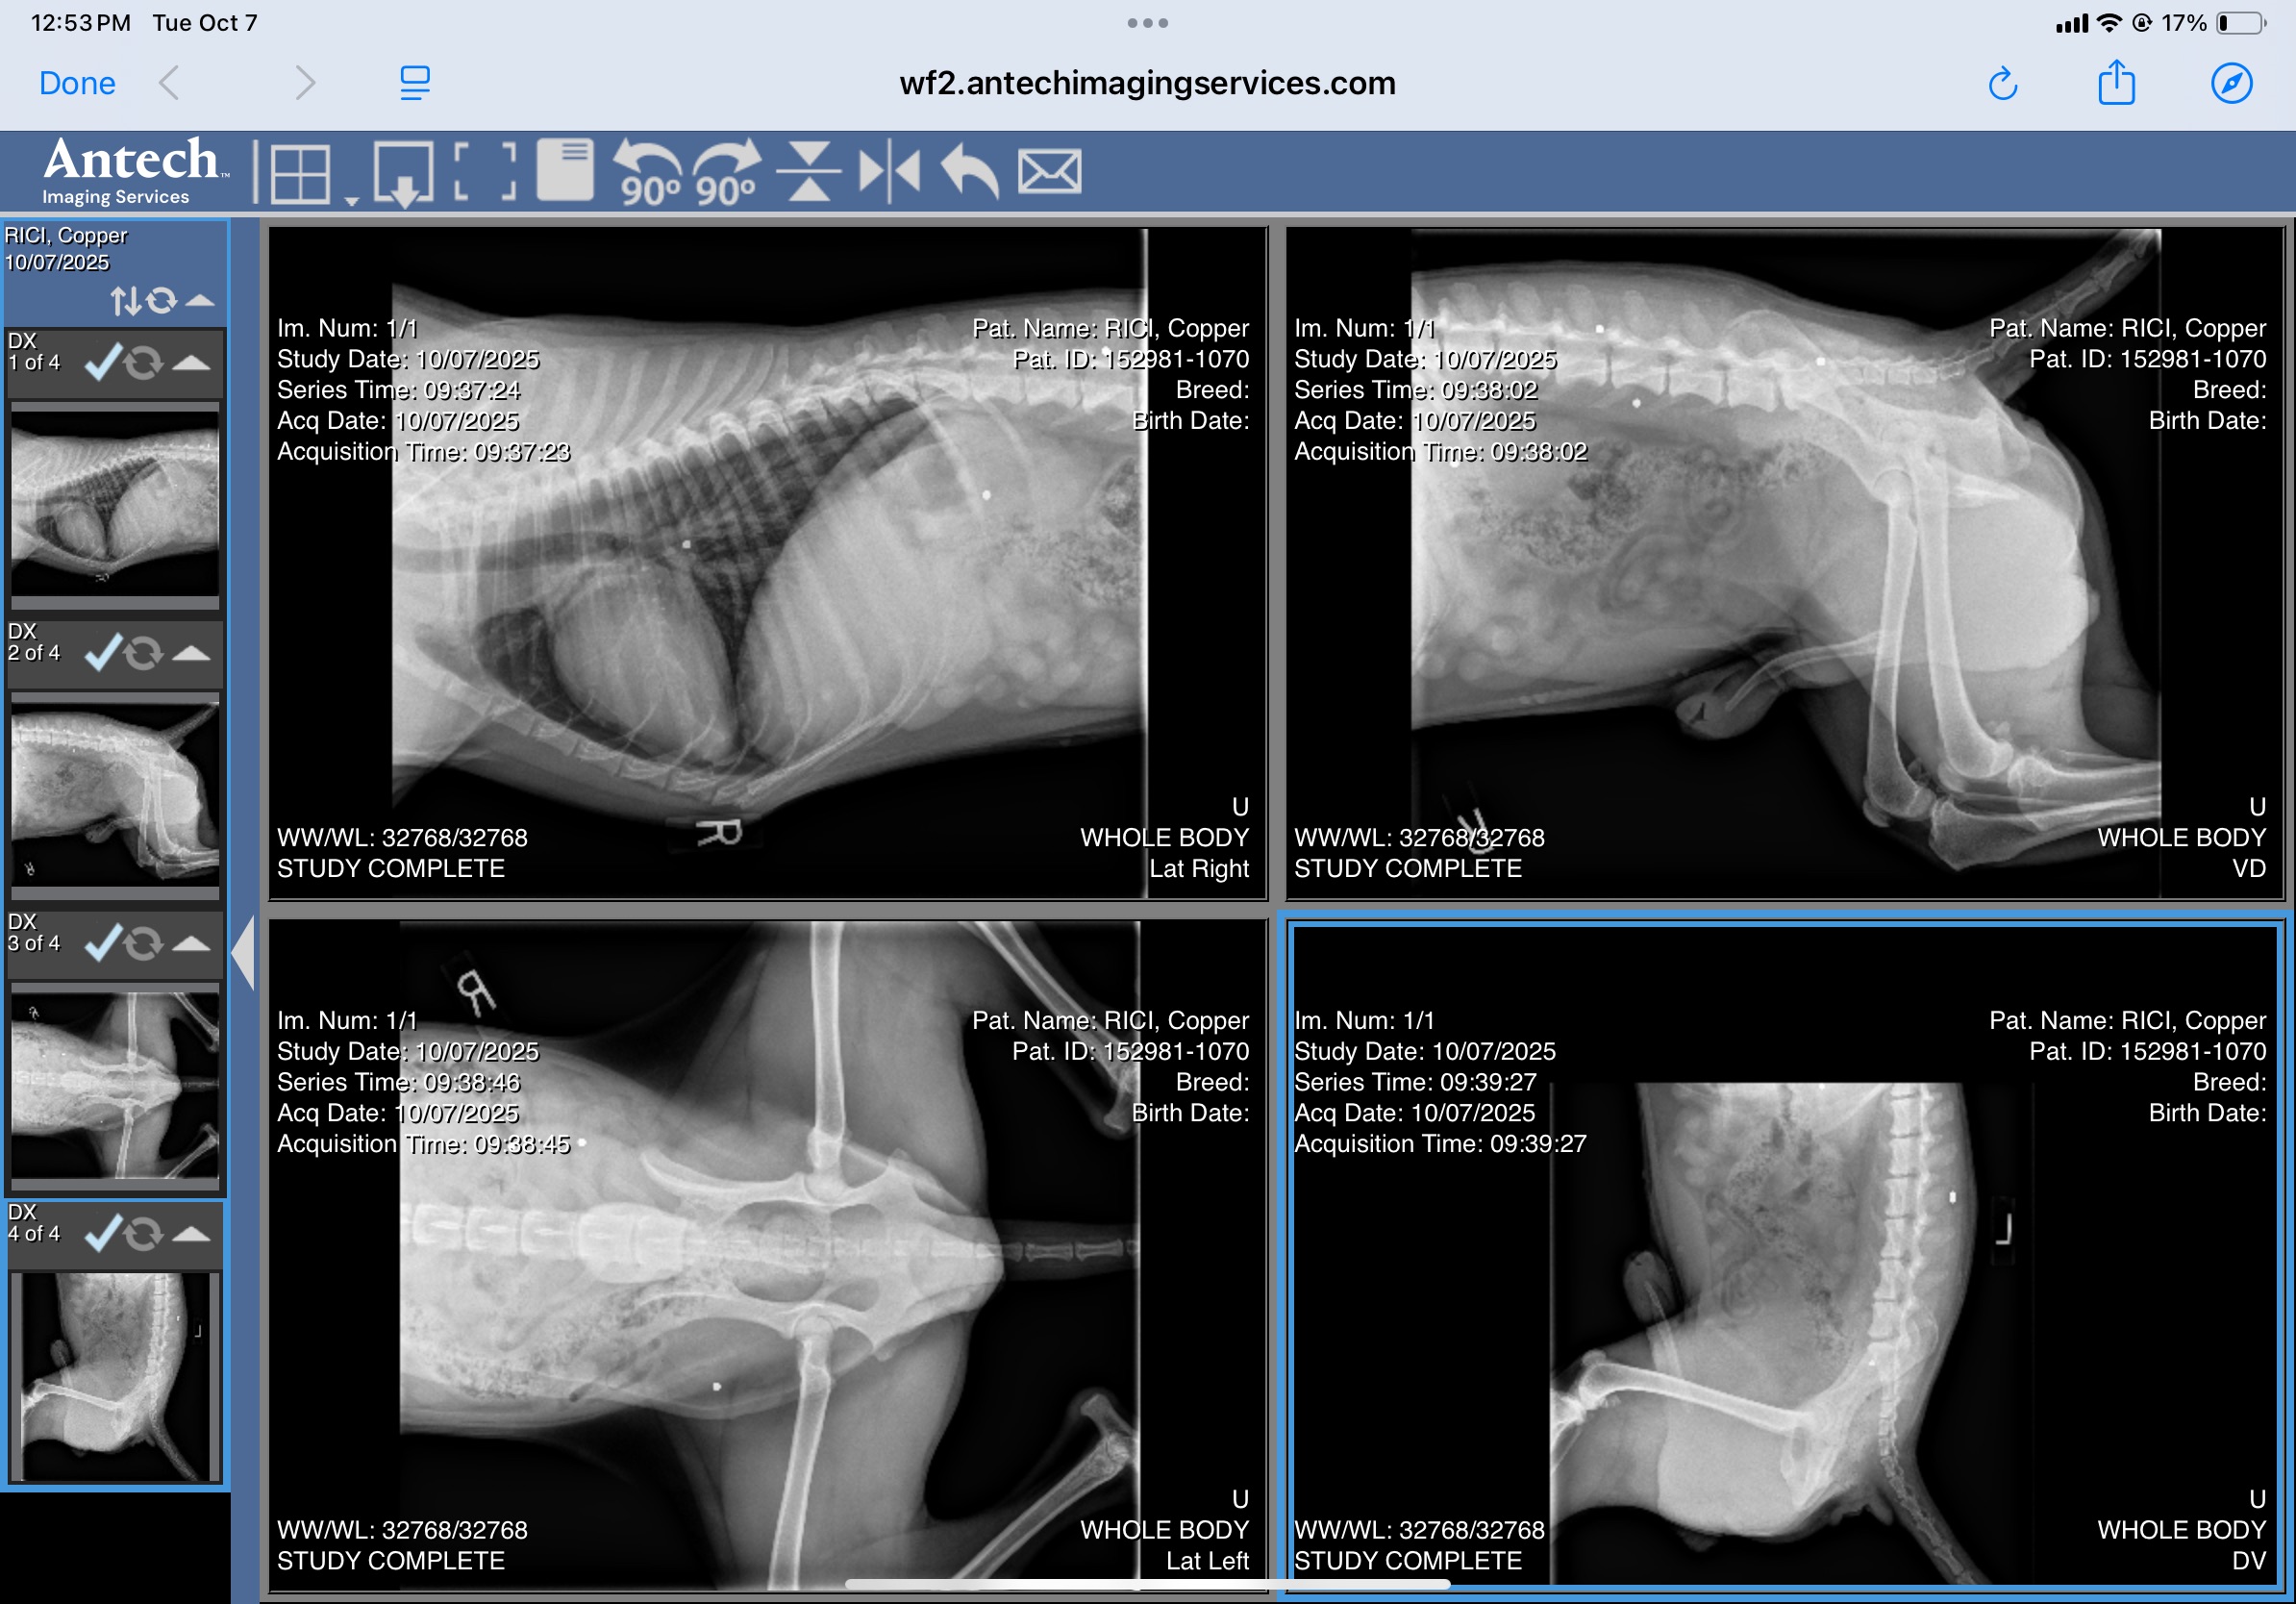

Copper is a very loving beagle/coonhound that was found in a very remote area.  He was taken to a vet to find that he had been shot multiple times with a pellet gun.  Copper has been treated, neutered and vaccinated.  He is a very loving beagle that just wants to love all over you.  He is great with other dogs and loves all humans.  He will chase cats.